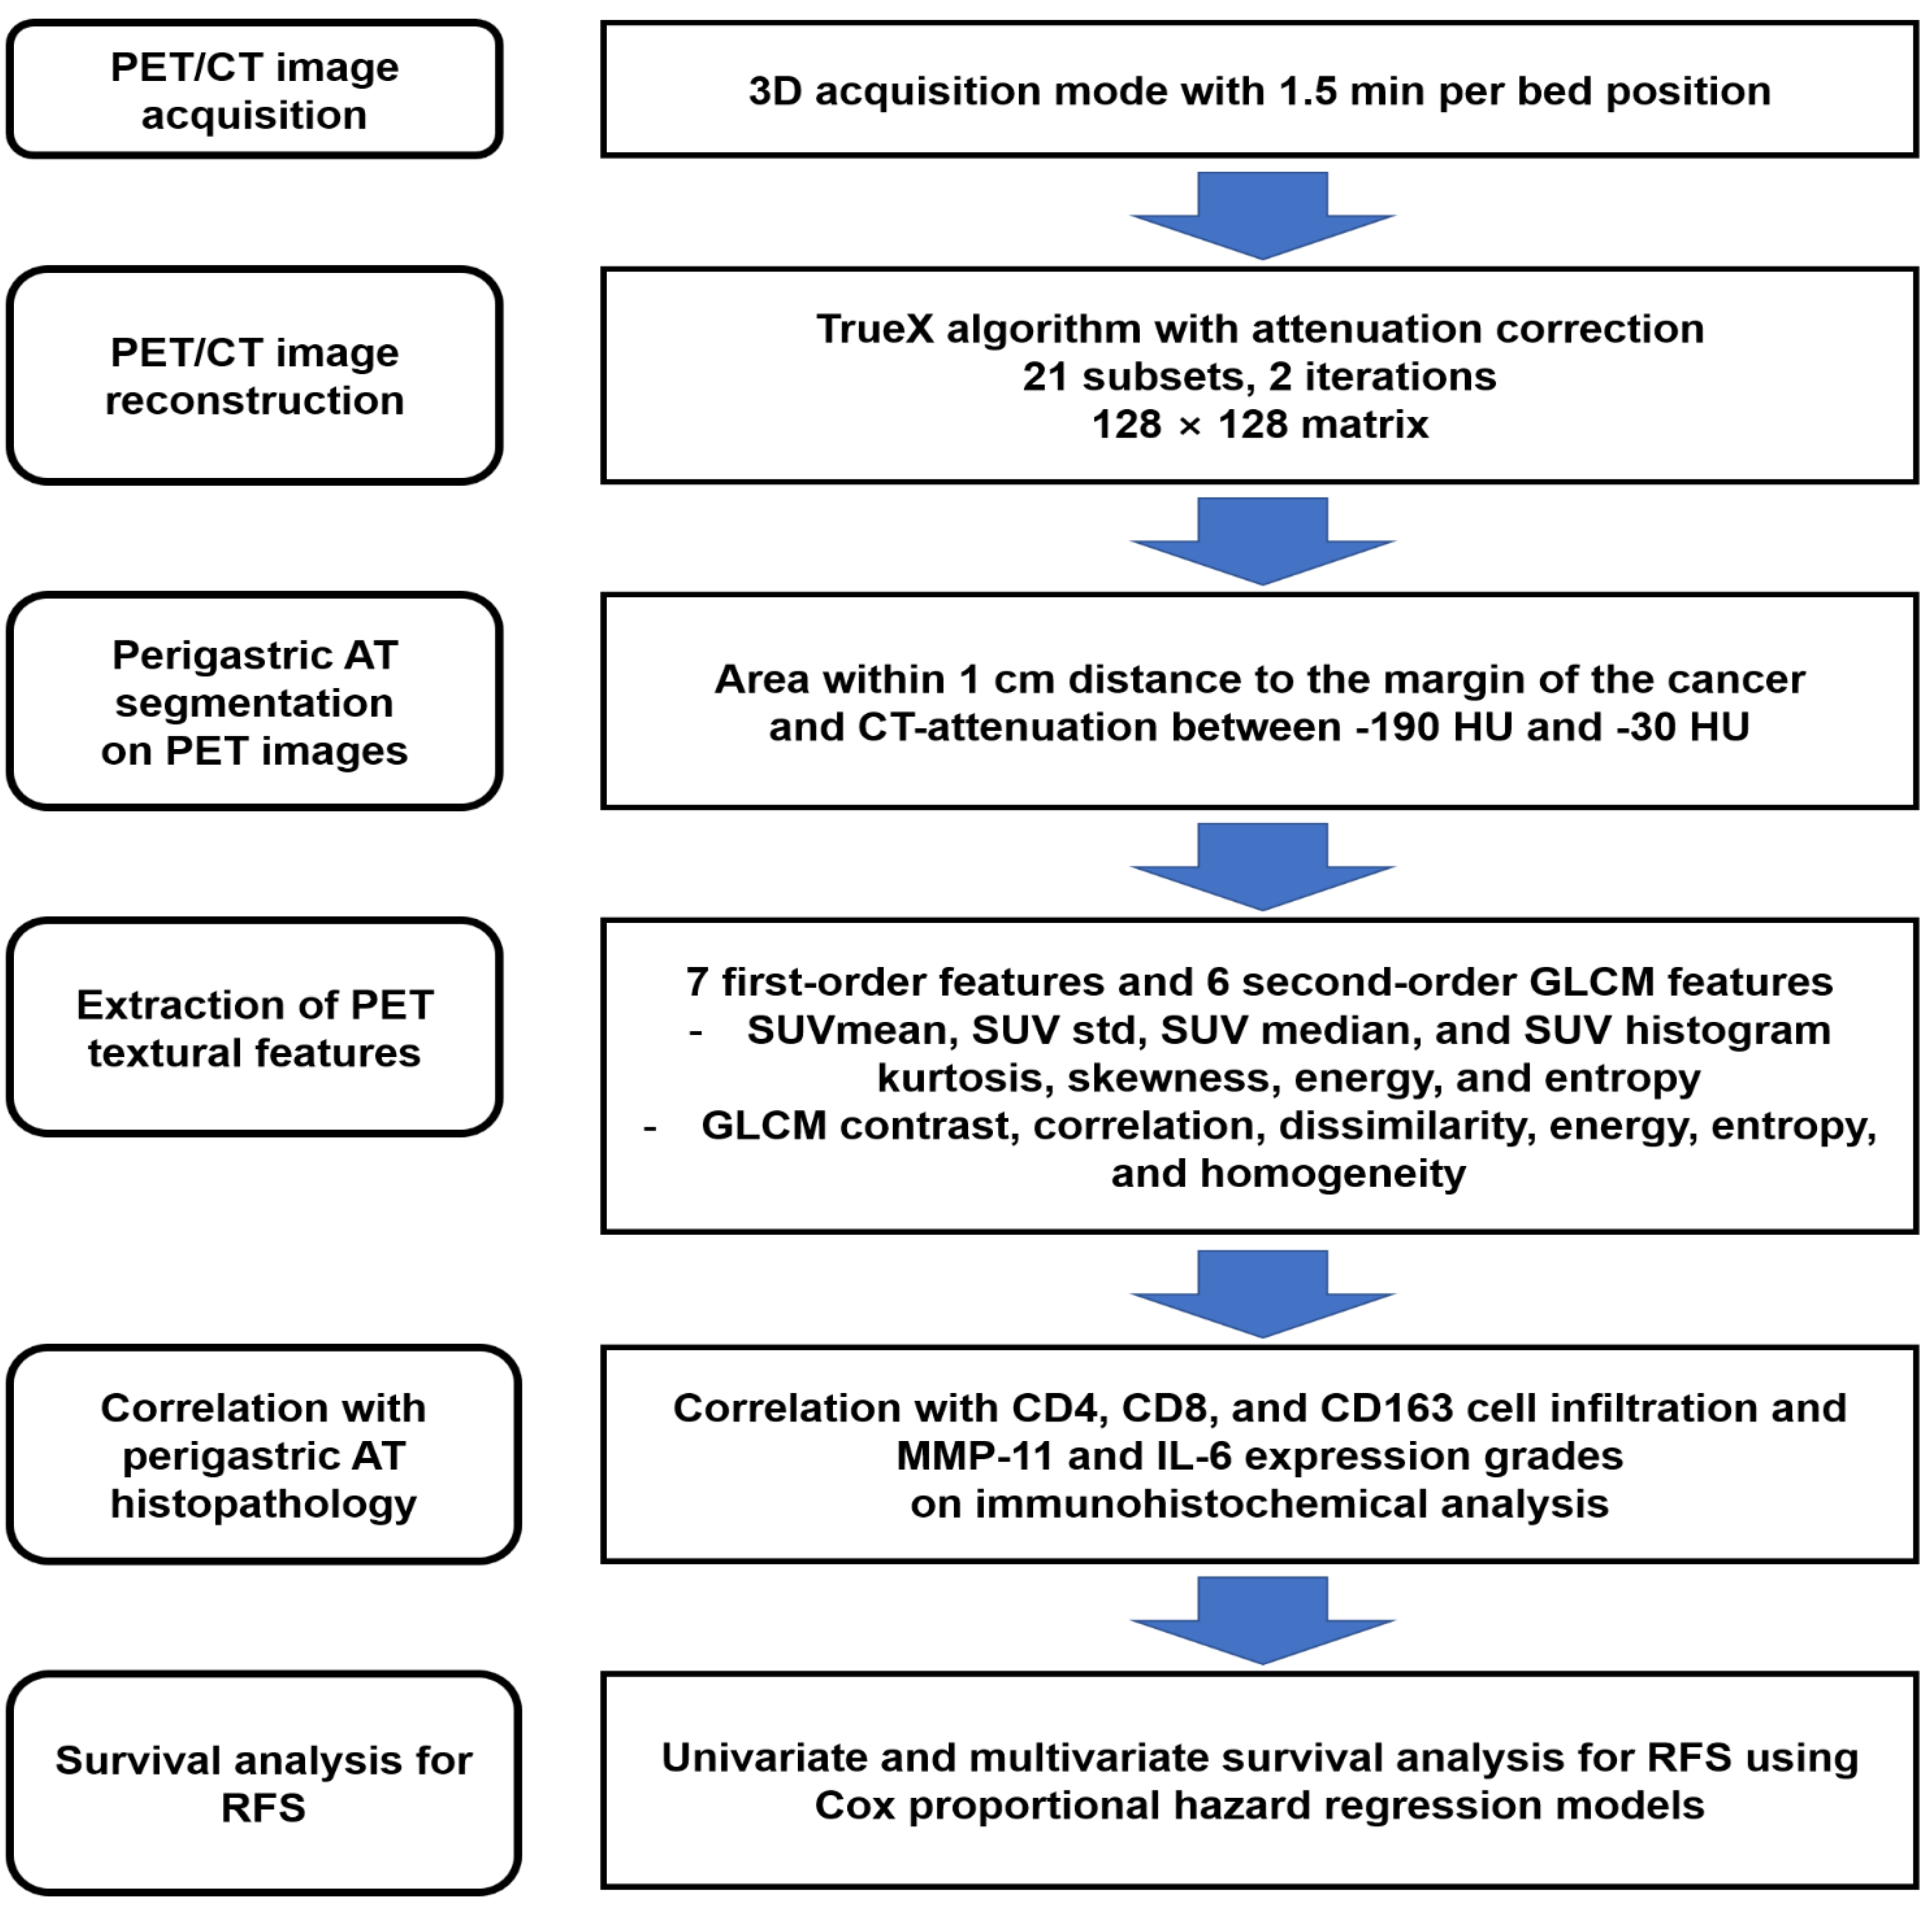

4. Materials and Methods

4.2. [18F]FDG PET/CT and Image Analysis

4.3. Histopathological Analysis

4.4. Statistical Analysis